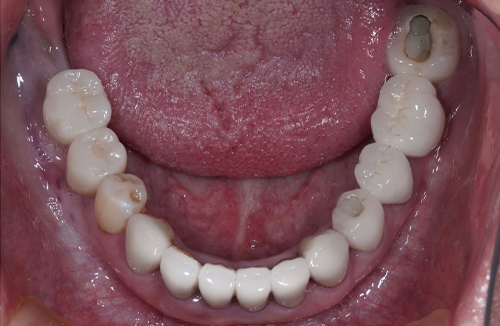

【お悩み】

奥歯を失ってから、食事の際にしっかり噛めず不便を感じていました。入れ歯には抵抗があり、インプラントを検討して来院されました。

【診断】

歯科用CT検査により、インプラントに必要な骨量が十分にあることを確認しました。

【治療内容】

骨造成は行わず、患者さまの状態に合わせたインプラント治療を行いました。

【治療後】

治療後は奥歯でしっかり噛めるようになり、食事のストレスがなくなったとお話しされています。

【この症例のポイント】

一般的な奥歯の欠損であれば、状態によっては比較的シンプルな治療計画でインプラントが可能なケースもあります。